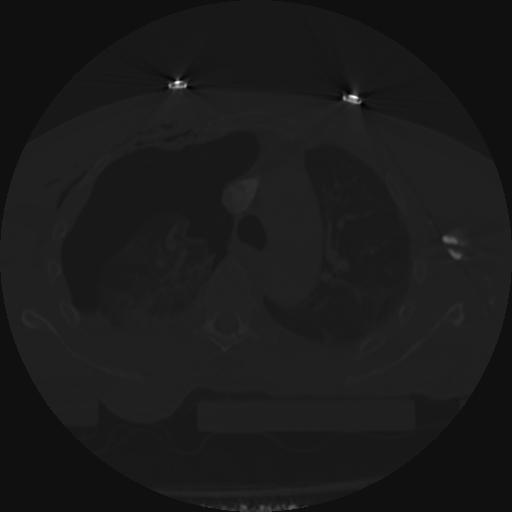

22 ANGIO,CE,Vol,0.5,ANGIO,,